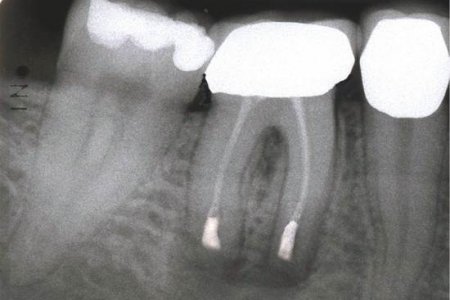

Endodontik müalicə (kanal müalicəsi) həyata keçirilən dişlərdə, kök kanallarının mürəkkəb konfiqurasiyası, yalnış və ya yetərsiz müalicə metodunun tətbiqi, bəzən də həkim səhvi/ehtiyatsızlığına bağlı olaraq təkrar iltihablanma – apikal ostit meydana çıxa bilir. Çox zaman bu tip iltihabi proseslər kliniki olaraq şikayətlərə səbəb olmadığından, zaman keçdikcə miqyasını genişləndirərək iltihab mənşəli odontogenik kistlərin yaranmasına gətirib çıxarır.

Bu zaman bəzi hallarda kanal müalicəsinin yenidən icrası (endodontik reviziya) mümkün olsa da, bir çox hallarda bu və ya digər səbəbdən həyata keçirilməsi mümkün olmur. Bu zaman əsas tətbiq edilən müalicə metodu dişi çəkməmək şərti ilə, iltihab ocağının uzaqlaşdırılmasını təmin edən – diş kökünün rezeksiyası metodudur. Bu əməliyyat vasitəsilə iltihab ocağı diş kökü ilə birlikdə kənarlaşdırılır və kök kanalları xüsusi metodla yenidən işlənir və doldurulur. Əməliyyat əsasən yerli ağrısızlaşdırma altında, xüsusi böyüdücü vasitənin tətbiqi ilə həyata keçirilir.